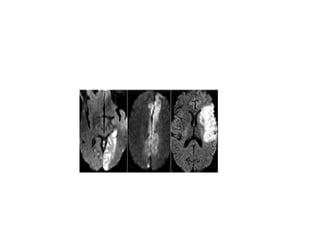

Diffusion Weighted Imaging (DWI)

DWI is the most sensitive sequence for stroke imaging.

DWI is sensitive to restriction of Brownian motion of

extracellular water due to imbalance caused by cytotoxic

edema.

Normally water protons have the ability to diffuse

extracellularly and loose signal.

High intensity on DWI indicates restriction of the ability of

water protons to diffuse extracellularly.